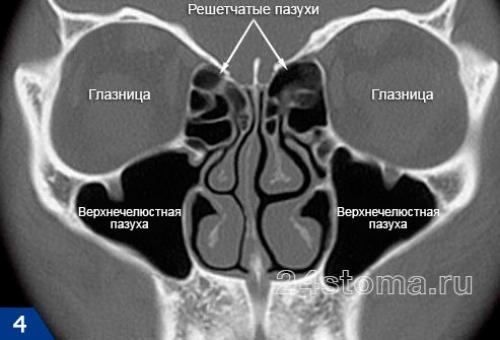

Синусит (от лат. sinusitis) – это воспаление слизистой оболочки, которая выстилает изнутри придаточные пазухи носа. Воспаление может локализоваться только в одной из пазух, либо сразу в нескольких. Чаще всего воспалению подвержены верхнечелюстные синусы (гайморовы пазухи), которые расположены в проекции верхушек корней 5-6-7 зубов с каждой стороны верхней челюсти. Такое заболевание принято называть терминами – верхнечелюстной синусит или гайморит (рис.2).

Синусит (помимо верхнечелюстных пазух) может также локализоваться в лобных пазухах, клиновидных пазухах, а также в ячейках решетчатой кости. Для его обозначения в этих случаях используются термины – фронтит, сфеноидит и этмоидит, соответственно. Однако, чаще всего пациентам приходится сталкиваться именно с верхнечелюстным синуситом, что связано прежде всего с некоторыми анатомическими особенностями верхнечелюстных пазух.